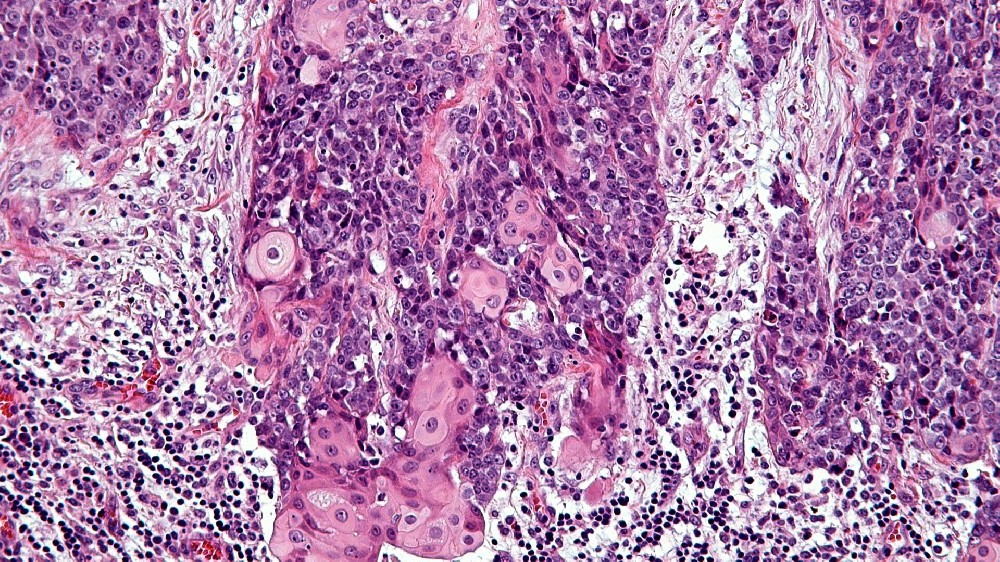

中線管癌 (NUT 癌症)是一種極為罕見但具侵略性的癌症,特徵為特定的基因突變。這種惡性腫瘤通常發生在身體的中線結構,如肺、縱膈、鼻腔或唾液腺,其特徵是位於 15 號染色體的睪丸核蛋白 (NUTM1) 基因重排。由此產生的基因改變會促進異常的細胞增殖和快速的腫瘤生長。

近年來,由 James P. Allison 教授和 Gregg Semenza 博士等知名諾貝爾獎得主所贊同的突破性研究,已闡明 NUT Carcinoma 的分子結構。這種癌症的表現主要是由於融合的染色體易位所致。 NUTM1 基因與 BRD4 或 BRD3 等基因,造成快速且無法控制的細胞分裂。

中線縱膈癌 (Midline Tract Carcinoma) 主要是由涉及 NUTM1 基因的特定基因易位所引起。與 BRCA1/BRCA2 基因突變相關的乳癌或 EGFR 基因突變相關的肺癌不同,NUT Carcinoma 特別涉及融合基因異常 (尤其是 NUT-BRD4)。雖然大多數患者不會遺傳這些突變,但已觀察到罕見的家族聚集,顯示個別病例有遺傳傾向。

鑑於中線縱膈癌 (Midline Tract Carcinoma) 中發現的特定基因融合 - BRD4-NUT 融合 - 新興的針對 BRD-NUT 互作的療法顯示出前景,有可能徹底改變治療方案:

Bromodomain 抑制劑(BET 抑制劑),如 molibresib 和 birabresib,專門針對 BRD4-NUT。